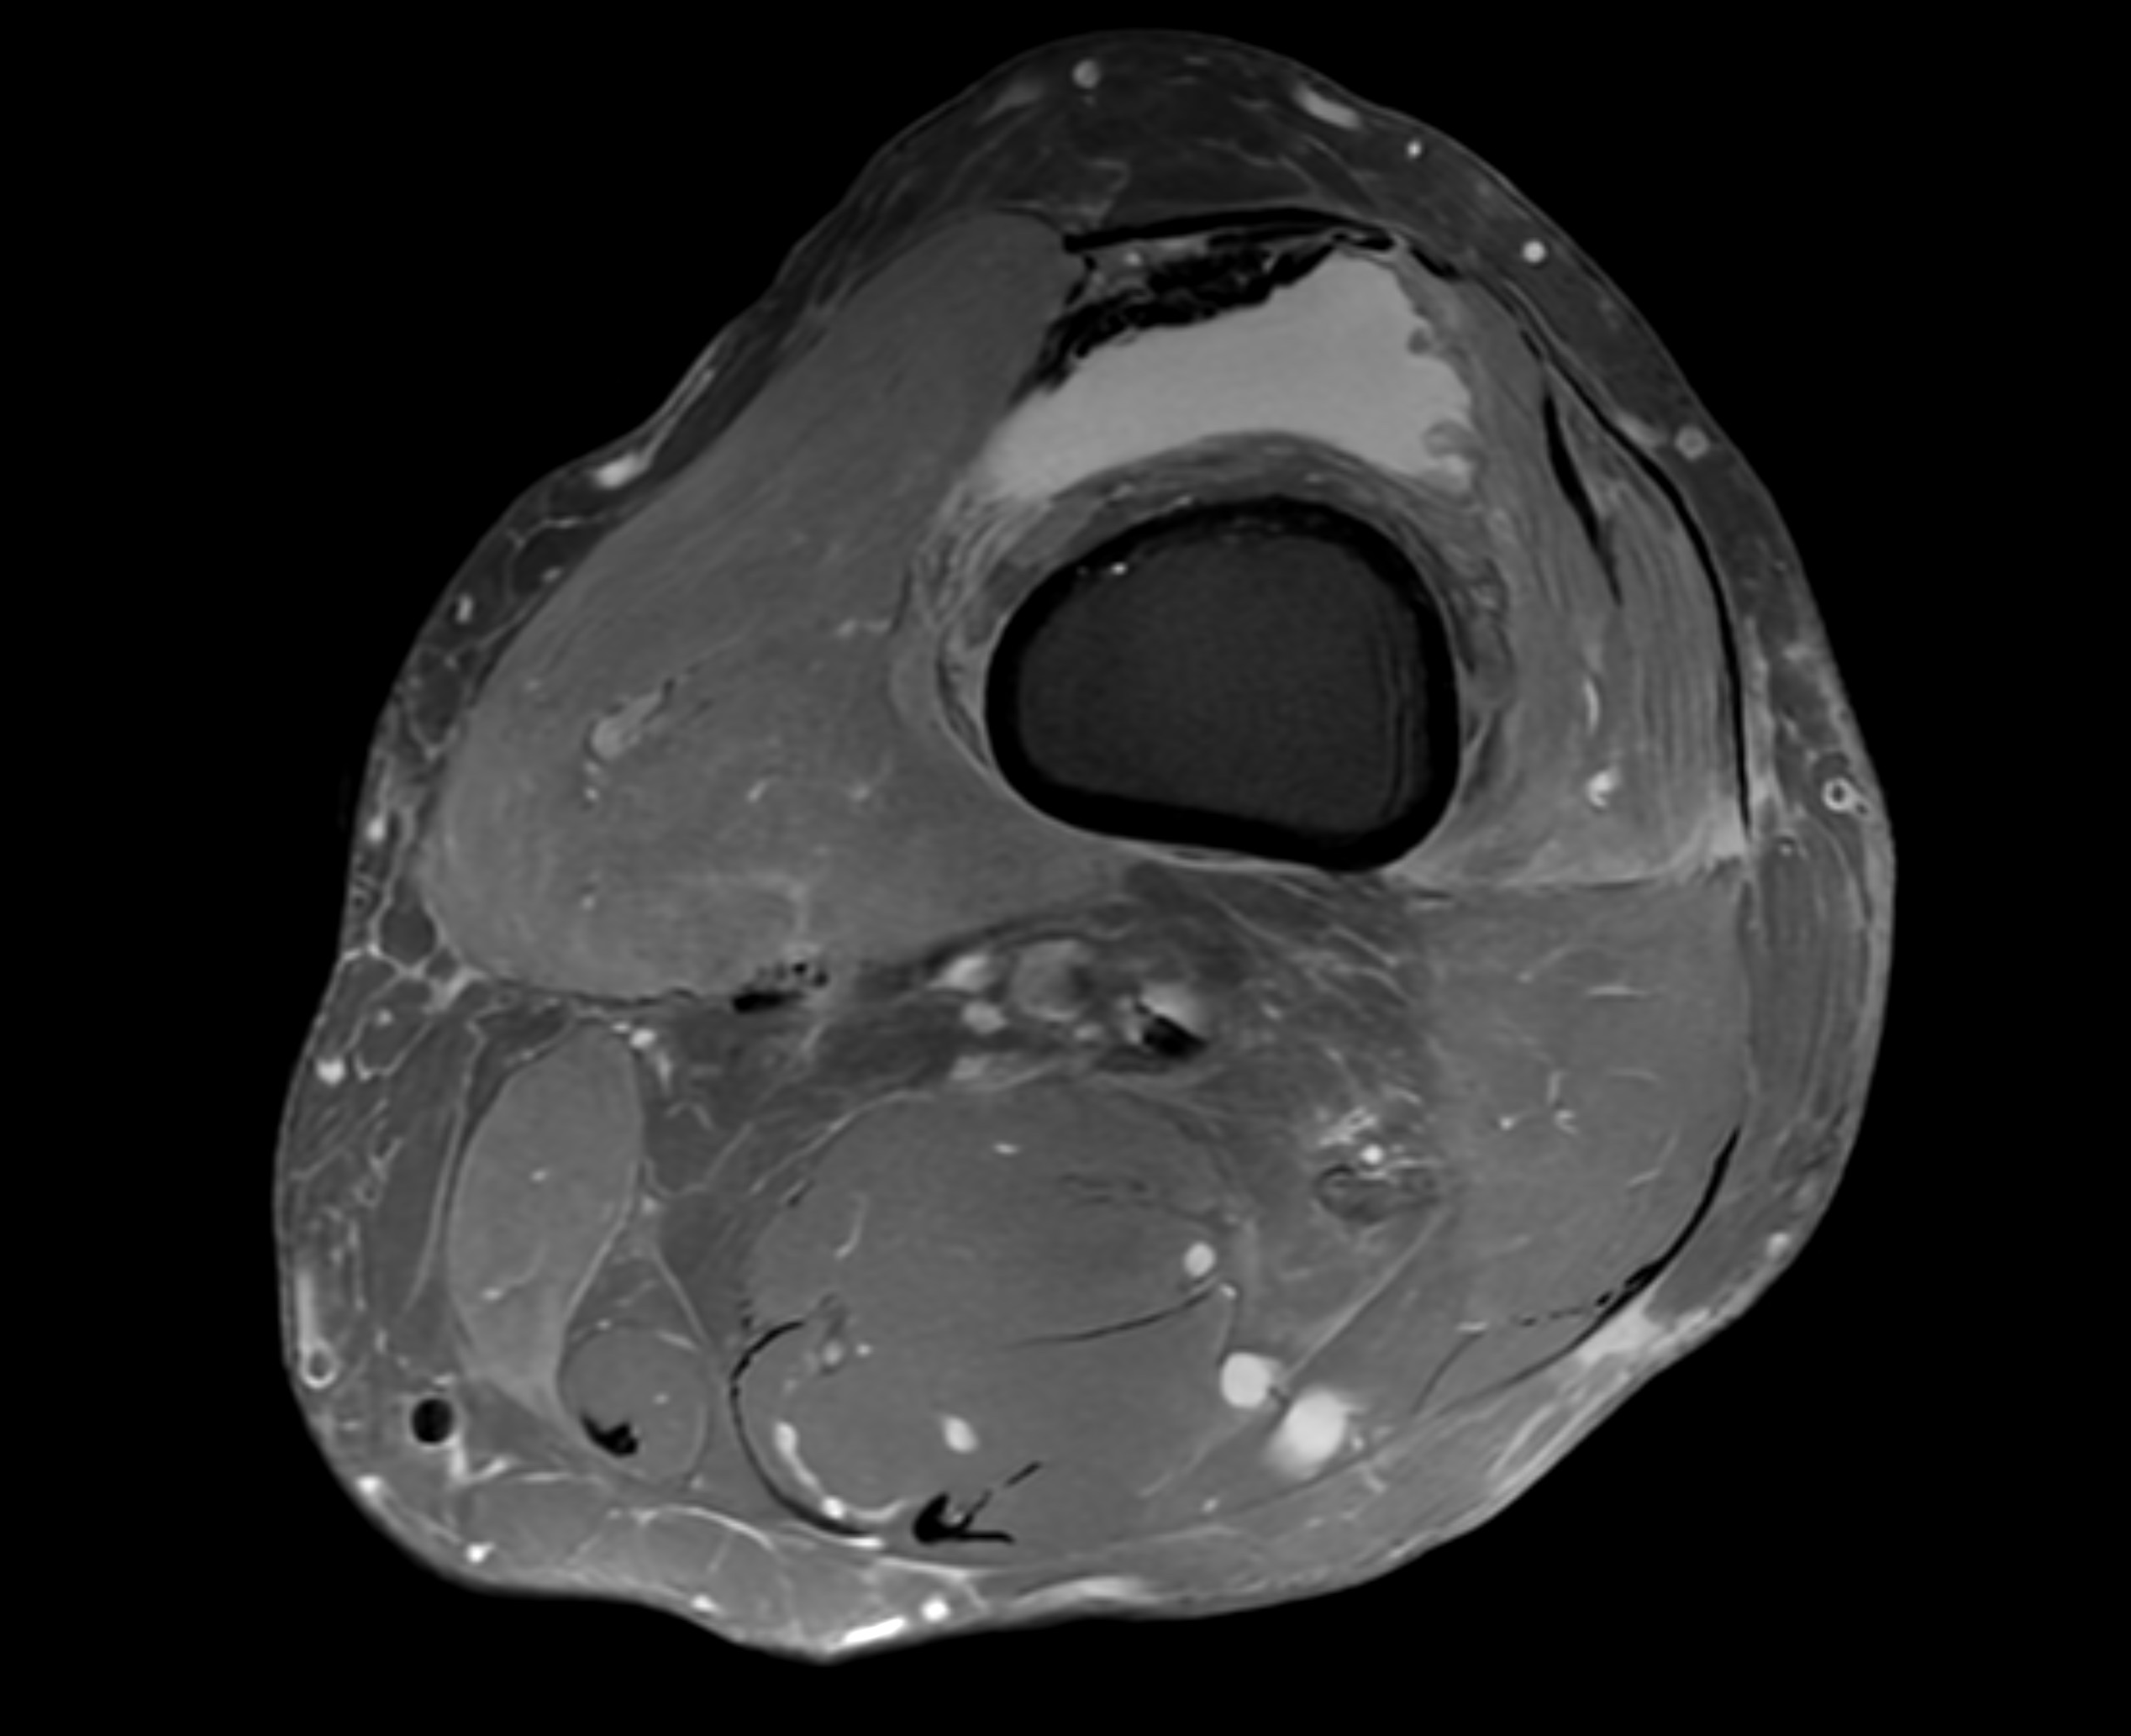

Knäleden är kroppens största och mest belastade led – en komplex struktur av ben, brosk, ledband, menisker, senor och slemsäckar som tillsammans möjliggör rörelse, stabilitet och stötdämpning. Det gör knäet särskilt utsatt för både akuta skador och förslitningar. Med en magnetkameraundersökning (MR) av knä eller knäled får man en mycket detaljerad bild av både skelett och mjukdelar. Undersökningen är helt utan strålning, smärtfri och överlägsen andra metoder när det gäller att upptäcka meniskskador, korsbandsskador, broskförändringar, artrit eller seninflammation.

MR knä rekommenderas särskilt vid ihållande smärta, svullnad, instabilitet eller om du misstänker en inre knäskada efter idrott, vridning eller olycka. Du kan boka direkt – utan remiss – och få tid inom några dagar.